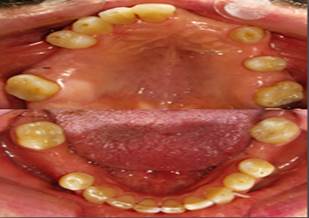

El paciente refiere no presentar hábitos tóxicos como tabaquismo o ingesta de alcohol. Este paciente fue clasificado como ASA II. A la exploración extraoral se evidenció paciente normocefálico, implantación capilar androide con tercios proporcionales, piel perioral sana y perfil recto, sin alteraciones relevantes. A la exploración intraoral presentaba ausencia de órganos dentarios 21, 22, 23, 24, 26, 28, 15, 16, 18, 45, 46, 48, 36, 38 (Figura 1).

Atrición dental en órganos anterosuperiores y anteroinferiores (Figura 2), al examen periodontal presentó recesiones gingivales en órganos dentarios 14, 17, 23, 25, 27, 33, 35, 41, 44, 47, sangrado en 34, 27 y 13, no se evidenciaron bolsas periodontales, lesiones de furca ni movilidad. Se procedió a realizar montaje en articulador con el fin de analizar oclusión del paciente y realizar un plan de tratamiento el cual consistió en rehabilitación con prótesis fija completa superior e implantes para reemplazar órganos dentarios 36 y 46.